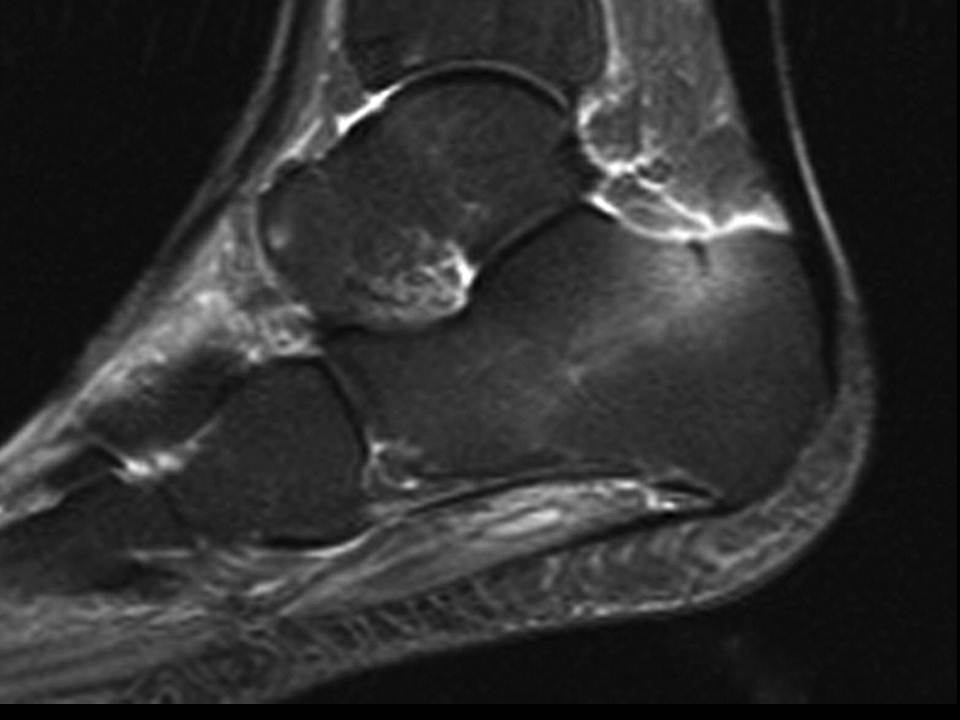

Cortisone Shot For Foot Stress Fracture . It's common in athletes and people who try to do too much activity too quickly. It can visualize lower grade stress injuries. treat the area with the rice method. getting the shot? Nerve, tendon, joint and fascial injuries seem to respond best to a local corticosteroid. if you suspect a stress fracture in your foot, performing what’s called 'the hop test' is a good way to figure out if you have point tenderness. stress fracture should be suspected in persons with a drastic recent increase in physical activity or repeated excessive activity with limited rest. stress fractures start as inflammation on a bone’s surface (healthcare providers call this a stress reaction). When you have a stress fracture, appropriate first aid can help minimize inflammation. an mri is considered the best way to diagnose stress fractures. Stress reactions are like deep bone. a new style of shoe can lessen your foot's ability to absorb repetitive forces and result in a stress fracture. a stress fracture in the foot is an overuse injury.